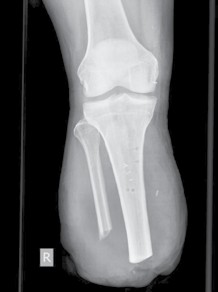

Knochenkanten, Exostosen und heterotope Ossifikationen treten nicht selten nach Amputationen auf. Diese Folgen könnten evtl. durch achtsamen Umgang mit dem Knochen und dem dazugehörigen Periost während der Amputation verhindert werden. Bei der Osteotomie des Knochens sollte beachtet werden, dass das Ende nicht schräg und spitz gesägt wird, sondern derart, dass eine möglichst große lasttragende Fläche gebildet wird und die Kanten sorgfältig abgerundet werden. Ferner sollte das Periost nicht exzessiv gestrippt und Periostfetzen liegen gelassen werden. Ein weiterer Fehler die Unterschenkelamputation betreffend besteht darin, die Fibula länger zu belassen als die Tibia. Des Weiteren darf die Osteotomieebene der Fibula nicht falsch angesetzt werden (Abb. 3). Beim kurzen Unterschenkelstumpf sollte die proximale Fibula zudem nicht belassen werden, da die fehlende Membrana interossea zu einer Hypermobilität der restlichen Fibula führen kann. Bei Vorliegen einer solchen Instabilität kann zunächst versucht werden, den Schaft auszubessern und der hypermobilen Fibula ausreichend Platz zu geben. Falls dies nicht zur Beschwerdefreiheit führt, sollte die restliche Fibula vollständig reseziert werden.